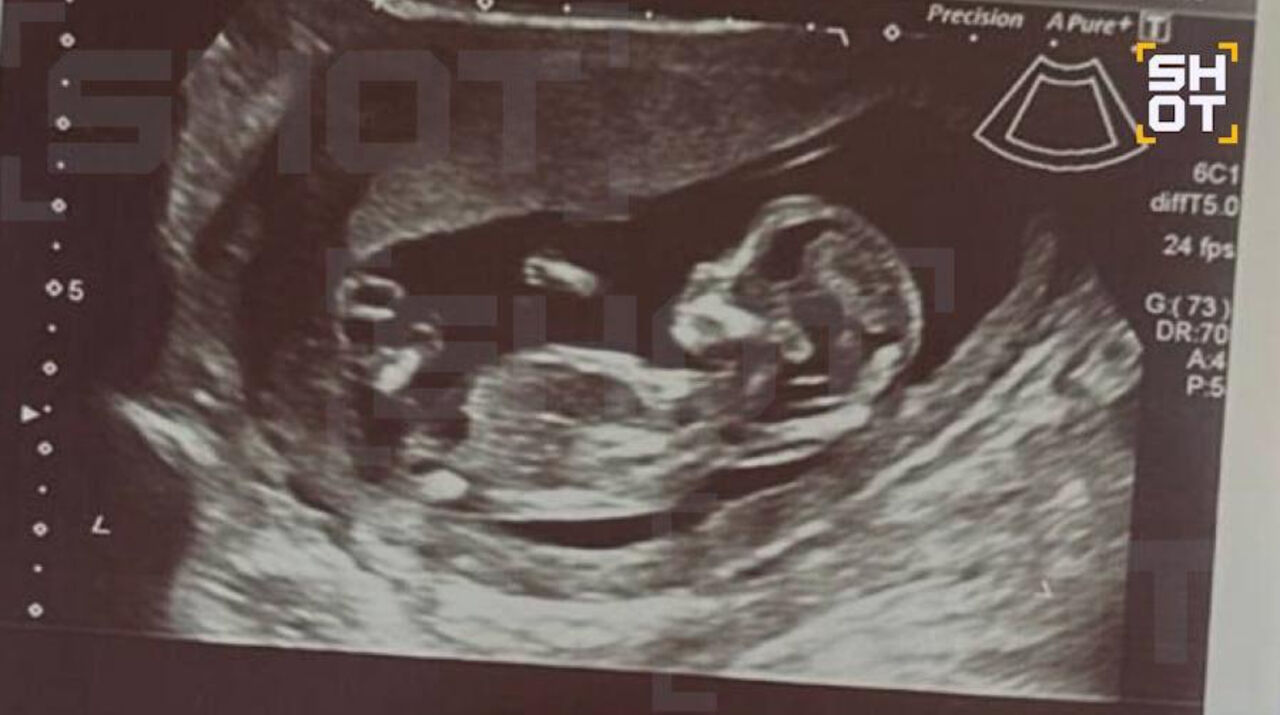

Выяснилось, что во время операции девушка уже была на пятой неделе беременности: ребенок пережил наркоз и воздействие множества лекарственных препаратов в восстановительный период. Эксперты предупреждают, что на пятом месяце развития формируются важнейшие органы, и вмешательство могло отрицательно сказаться на этом этапе.

Telegram-канал SHOT сообщает, что сейчас девушка регулярно посещает врача, беременность протекает нормально.

Фото: Telegram / SHOT